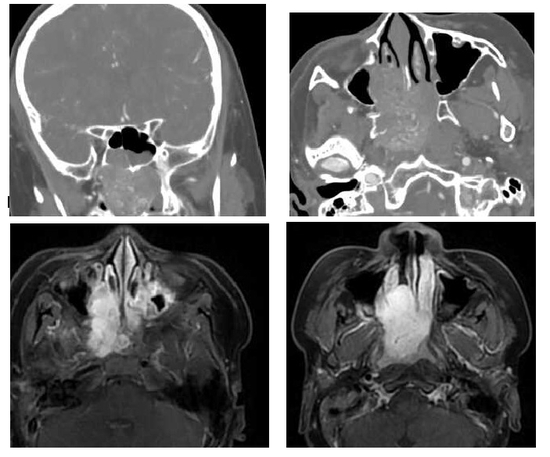

耳鼻咽喉科副主任陈海红主任医师接诊浩浩后,发现他右侧鼻腔里有暗红色光滑肿物,与张先生交流过后,为浩浩进行鼻窦CT+三维重建、鼻咽部增强磁共振MR检查后,浩浩被诊断为“鼻咽纤维血管瘤”,瘤体约有稍稍压瘪的乒乓球大小(5.2*3.0cm),占据鼻腔后端、鼻咽部,突入蝶窦、翼腭窝。“这颗肿瘤紧贴颌内动脉,血供丰富、触之极易大出血,有很大的手术风险。” 陈海红主任医师介绍,小孩子的皮肤稚嫩、鼻粘膜糜烂后, 往往被认为是鼻窦炎而漏诊,必须结合鼻内镜检查、结合鼻窦CT和鼻部MR才能精准判断,经科室大讨论后,团队决定对浩浩先栓塞以减少肿瘤血供,而后开展手术。

11月8日,由放射科彭志毅主任医师团队给浩浩在局部麻醉下进行右颈外动脉造影+栓塞术。次日,由陈海红主任医师主刀,在鼻内镜下应用等离子刀阻断肿瘤滋养动脉,在不到2小时的时间呢完整切除整个肿物,手术中出血极少,经病理检查,结果符合鼻腔血管纤维瘤。还好这种肿瘤是良性的,手术后的浩浩恢复良好,再也没有鼻塞、流鼻血,夜里睡觉也不憋气了,术后第4天,张先生就带着浩浩平安出院。

这种瘤,尤其偏爱青春期男少年

无独有偶,今年13岁的绍兴上虞男孩明明,也遭遇了和浩浩相似的情况,一直鼻塞、反复鼻出血。在绍兴当地医院治疗效果不佳后,他被转诊至浙大一院耳鼻喉科。经过详细检查,明明同样遭遇“鼻咽纤维血管瘤”,肿瘤破坏了他的颅底骨质。这时,明明的双侧鼻腔、鼻道已经被肿瘤充满,他只能够靠嘴来大口呼吸。

11月14日,由陈海红主任医师主刀,程可佳副主任医师协助,通过鼻内镜下行鼻-颅底鼻咽纤维血管瘤切除术,顺利切除了明明的巨大肿瘤。